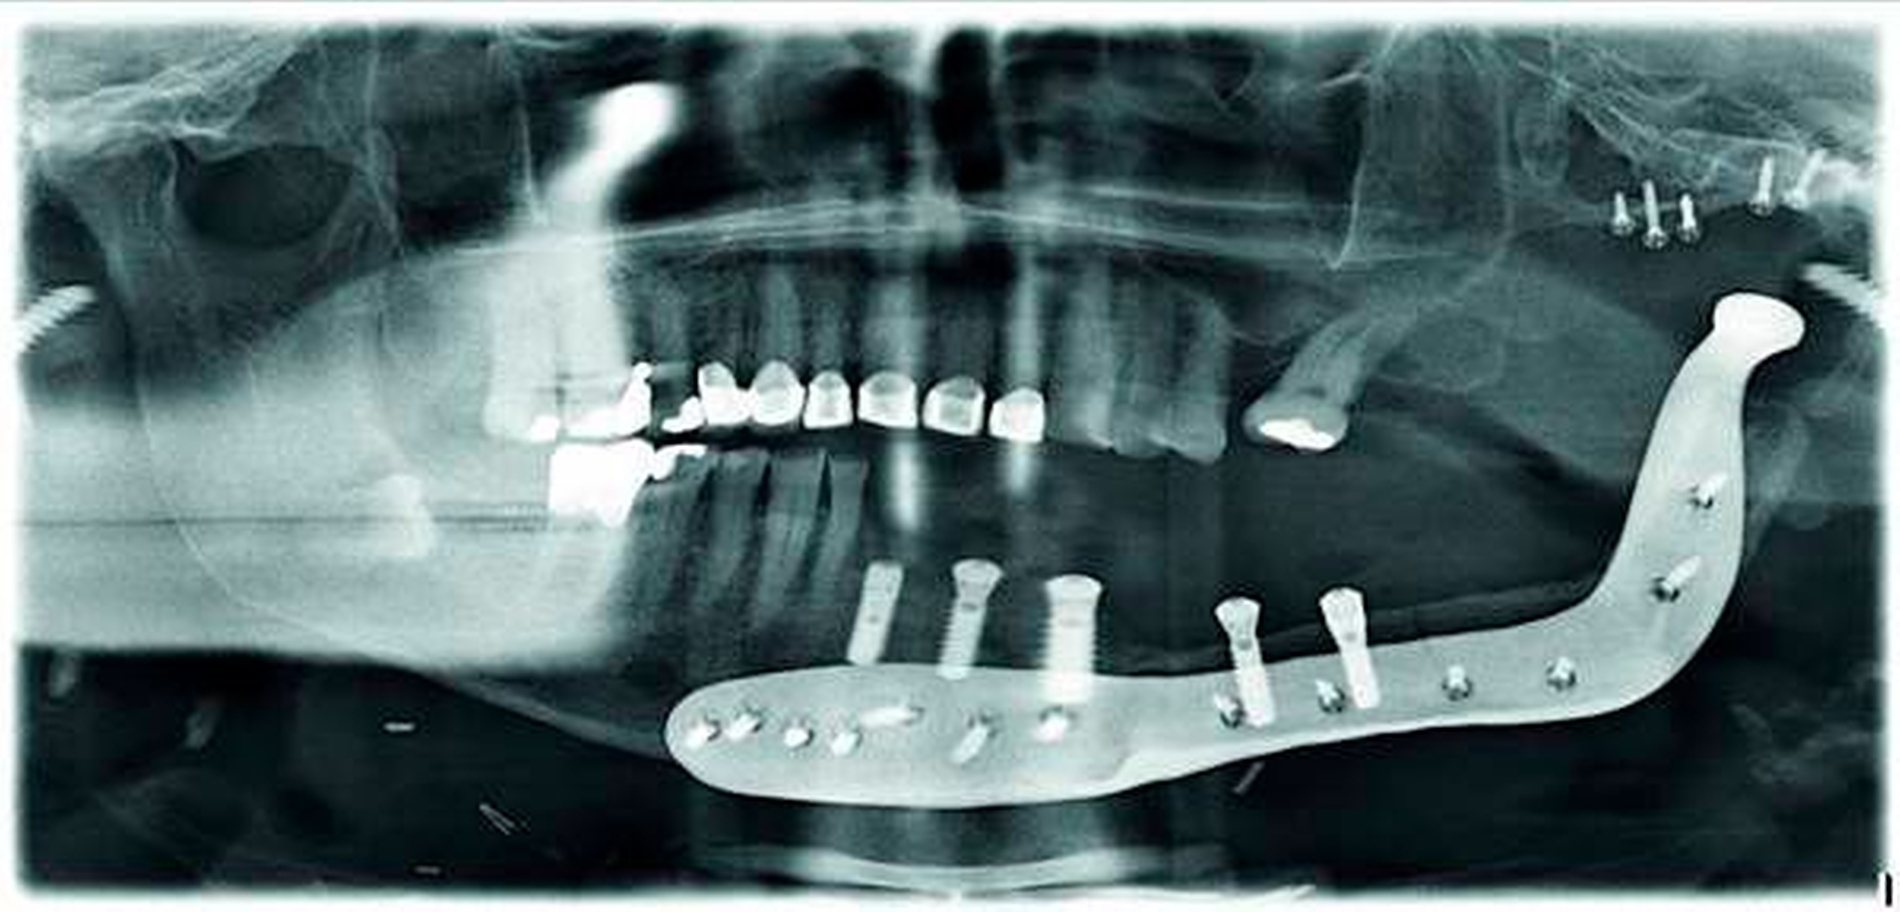

Im Intervall begann die Planung der notwendigen dentalen Implantation. Wir haben uns für die Verwendung von Implantaten der Firma Straumann (Institut Straumann AG, Basel, Schweiz) entschieden. Dem Behandler wird ein großes Portfolio an unterschiedlichen Implantat-Designs und entsprechenden prothetischen Aufbauten zur Verfügung gestellt, das bei komplexen Fällen notwendig werden kann. Im ersten Schritt stellte das zahntechnische Labor Schuldes (Dental Labor Schuldes GmbH, Eisenach) eine Scanschablone her, mit der die CT durchgeführt wurde (Abbildung 11).

Nachfolgend konnte im Backward-Planning mit der Planungssoftware coDiagnostiX (Dental Wings GmbH, Chemnitz) die möglichst optimale Position der Implantate in Bezug auf die transplantierte Fibula und Gegenkiefer festgelegt werden (Abbildung 12). Es erfolgte die Umwandlung in eine full guided-Bohrschablone für das Straumann Guided Surgery System.

Entsprechend der Planung wurden fünf Straumann-Implantate im full guided-Verfahren in die verbliebene Mandibula und die Neomandibula inseriert. Das regio 41 eingebrachte Implantat ist durch Blut überdeckt (Abbildung 13).

Abbildung 14 zeigt das postoperative OPG. Durch die optimale Planung konnte die Kollision von Implantaten, PSI und Fixationsschrauben vermieden werden, was somit die Implantation erst möglich machte.